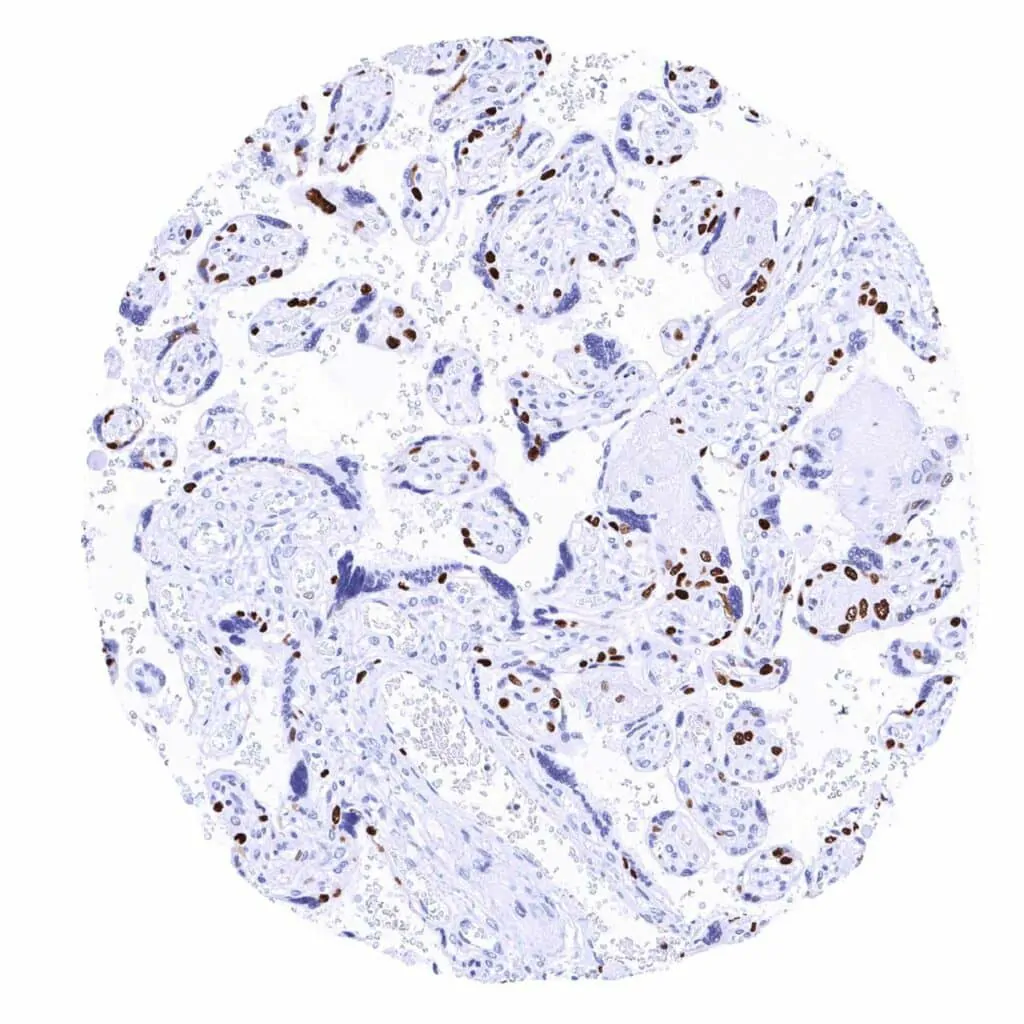

Placenta, early – Strong MCM2 staining of a large fraction of cytotrophoblast cells